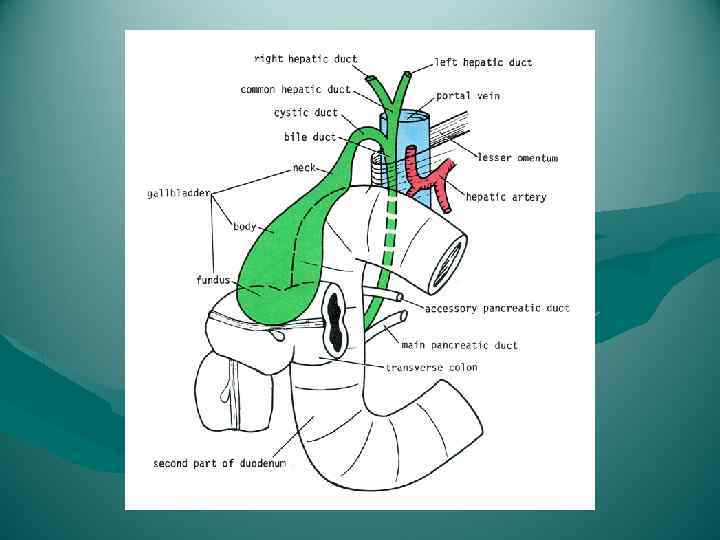

Связочный аппарат печени Нижняя поверхность печени связана с малой кривизной желудка и верхней частью двенадцатиперстной кишки непрерывной дупликатурой брюшины — печеночножелудочной, lig. hepatogastricum, и печеночнодвенадцатиперстной, lig. hepatoduodenale, связками. Ligg. hepatoduodenale, hepatogastricum et gastrophrenicum составляют малый сальник (omentum minus).

Связочный аппарат печени Нижняя поверхность печени связана с малой кривизной желудка и верхней частью двенадцатиперстной кишки непрерывной дупликатурой брюшины — печеночножелудочной, lig. hepatogastricum, и печеночнодвенадцатиперстной, lig. hepatoduodenale, связками. Ligg. hepatoduodenale, hepatogastricum et gastrophrenicum составляют малый сальник (omentum minus).

Взаимоотношение поджелудочной железы с двенадцатиперстной кишкой, общим желчным протоком, воротной и нижней полой венами, брюшной аортой и ее ветвями. 1 — v. cava inferior; 2 — aorta abdominalis; 3 — truncus coeliacus; 4 — a. gastrica sinistra; 5 — a. lienalis; 6 — v. lienalis; 7 — v. mesenterica inferior; 8 — a. mesenterica superior; 9 — v. mesenterica superior; 10 — caput pancreatis; 11 — duodenum; 12 — a. gastroduodenalis; 13 — a. hepatica communis; 14 — a. hepatica propria; 15 — ductus choledochus; 16 — a. gastrica dextra; 17 — v. portae; 18 — ductus cysticus; 19 — ductus hepaticus communis.

Взаимоотношение поджелудочной железы с двенадцатиперстной кишкой, общим желчным протоком, воротной и нижней полой венами, брюшной аортой и ее ветвями. 1 — v. cava inferior; 2 — aorta abdominalis; 3 — truncus coeliacus; 4 — a. gastrica sinistra; 5 — a. lienalis; 6 — v. lienalis; 7 — v. mesenterica inferior; 8 — a. mesenterica superior; 9 — v. mesenterica superior; 10 — caput pancreatis; 11 — duodenum; 12 — a. gastroduodenalis; 13 — a. hepatica communis; 14 — a. hepatica propria; 15 — ductus choledochus; 16 — a. gastrica dextra; 17 — v. portae; 18 — ductus cysticus; 19 — ductus hepaticus communis.